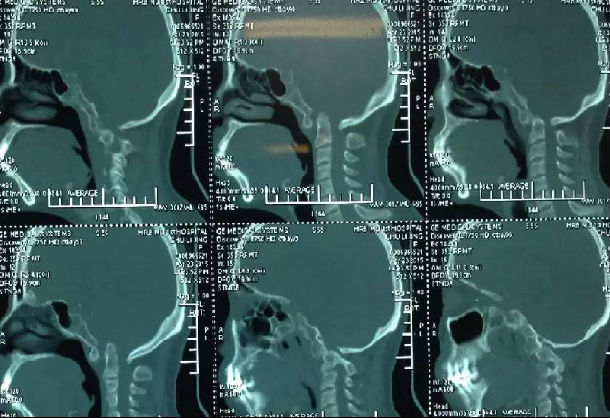

3影像学检查

手术前后伸前屈位X光片寰枢椎脱位为可复性(后伸位脱位复位,前屈位寰齿前间隙(ADl)大于5mm)。寰枢椎CT椎弓根发育良好(大于4mm),磁共振脊髓损伤伴椎管狭窄。

4术前片子

手术前前屈位X光片寰枢椎脱位(寰齿前间隙7mm)。寰枢椎三维CT见寰枕融合,颅底陷入(齿状突位于钱氏线上14.2mm),右侧枢椎椎弓根发育狭小(小于2mm),磁共振显示小脑扁桃体下疝、颈髓损伤伴椎管狭窄。